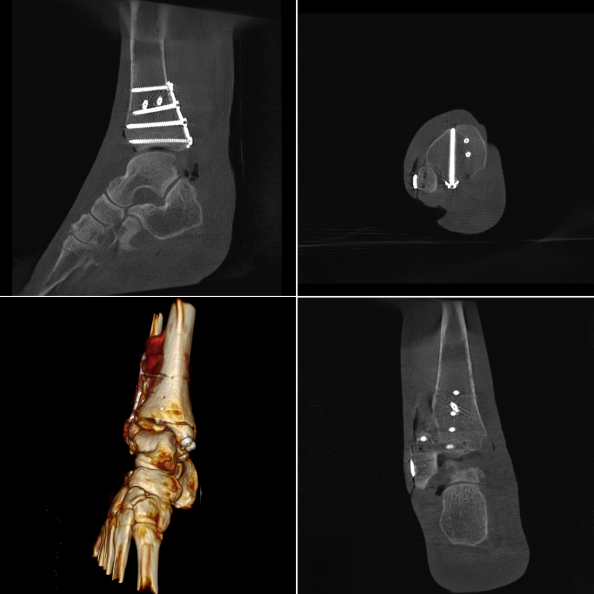

Les meilleures images cliniques du Ziehm Vision RFD 3D

Enhanced Screw Visualisation (ESV)

Localisation intuitive du positionnement des vis en imagerie 3D